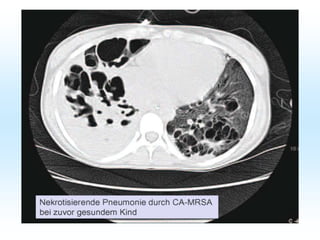

Erkrankungen des Lymphsystems: 1)Erysipel: Rötung und Schwellung der Unterhaut. und tiefere Schichten bakterieller Befall mit Beta-hämolysierenden Strptokokken, Eintrittspforten Haut, Therapie: Unacid 3x 3 g iv. Bei nekrotisieirender Faszikulitis: Leukos , TNF, BSG und Penicillinallergie -> Ausweichen auf Klacid iv.oder Erythromicin iv.zusätzlich NSAR und Behandlung der Begleiterkrankungen. 2) Lymphödem : strangartige Rötung der Lymphgefäße 10% hereditär, 85 % durch Infekt oder TU, ggf. Lympgdrainagen Therapie z.B. Sobelin . 3) Lymphangitis: Entzündung von Benachbartem Gewebe: Abstrich und Antibiose z.B Staphenor oder Sobelin iv. 4) Phlegmone: oberflächliche Entzündung der Haut z.B durch Phlebitis etc. 5)Abszeß tiefergehend abgekapselt , häufig von Haarbalg ausgehend. Furunkel-Karbunkel-Abszeß.